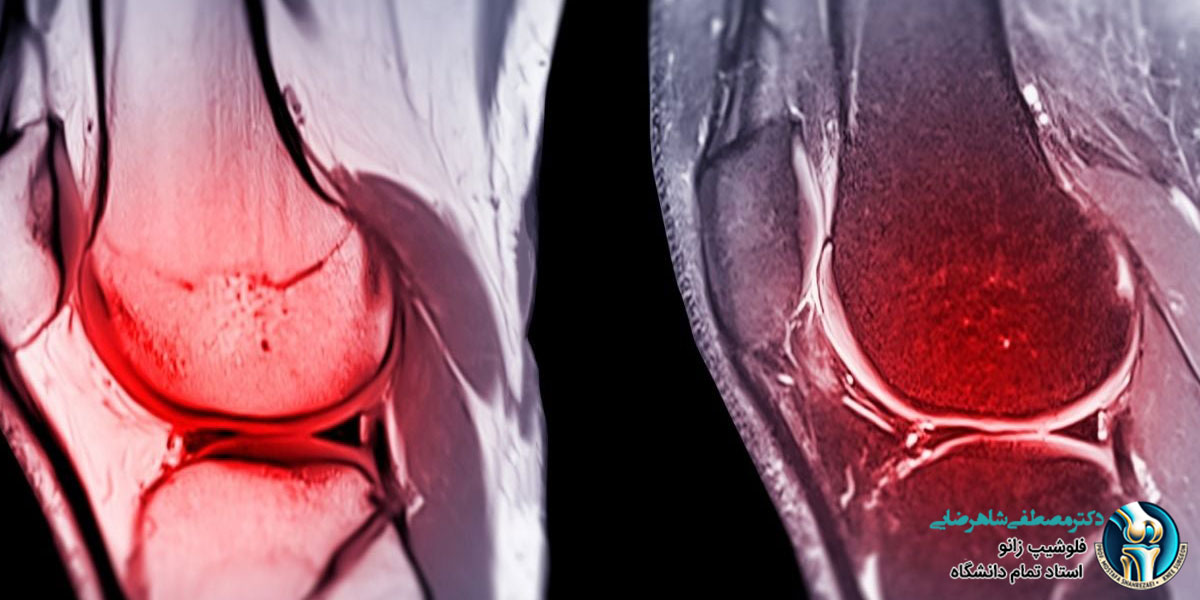

ام آر ای زانو یکی از تکنیک های تصویربرداری پیشرفته است که برای ارزیابی مشکلات زانو استفاده می شود. این تکنیک با استفاده از میدان مغناطیسی قوی و امواج رادیویی، تصاویر دقیق و برشی از ساختارهای داخلی زانو ایجاد می کند. با استفاده از ام آر ای زانو می توان مشکلاتی از قبیل شکستگی ها، آسیب های غضروفی و التهابات را تشخیص و ارزیابی کرد.

ام آر آی زانو یکی از تکنیک های تصویربرداری پیشرفته است که برای ارزیابی مشکلات زانو استفاده می شود. در جریان انجام این آزمایش، بیمار درون دستگاهی قرار می گیرد که میدان مغناطیسی قوی ایجاد می کند. سپس امواج رادیویی به بدن فرستاده می شوند و دستگاه بازتاب آن ها توسط بافت های داخلی زانو را دریافت و به تصویر تبدیل می کند. این فناوری مشکلاتی مانند شکستگی ها، آسیب های غضروفی، التهابات و نقرس را نشان می دهد و برای ارزیابی عملکرد زانو بعد از جراحی های زانویی مانند جراحی رباط صلیبی یا ترمیم غضروف، مورد استفاده قرار می گیرد.

• دقت و وضوح تصاویر: تصاویر ام آر آی زانو با جزییات بسیار دقیق و وضوح بالا از ساختار زانو ارائه می دهند که به پزشکان کمک می کند تا به طور دقیق تر تشخیص دهند.